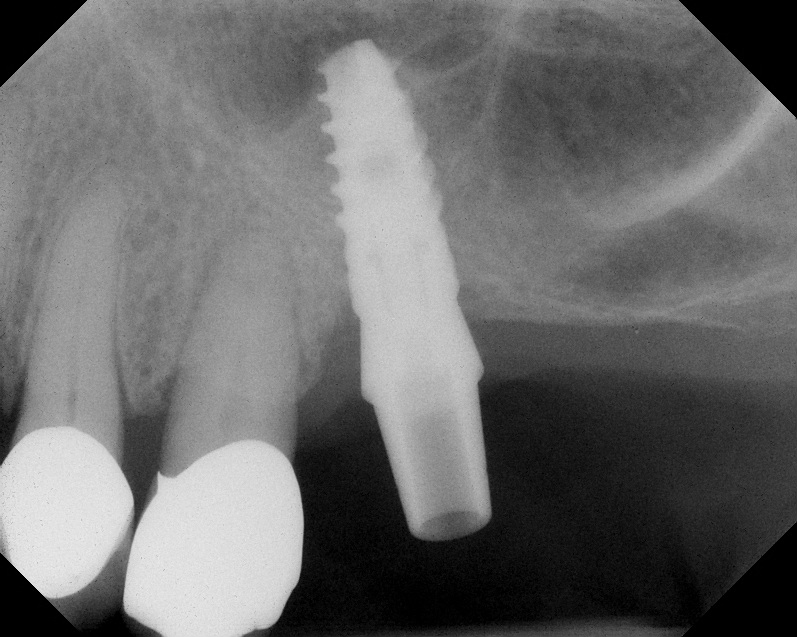

A 74-year-old male patient presented with about 4 mm to 5 mm of native bone in the No. 4 position (Figure 17). A composite graft, as described in Case 1, was used, as was the same implant type, but the implant was 11.5 mm in length with a taper of 5 mm to 4.2 mm. The approximately 16-month post-healed floor of the sinus was raised about 7 mm to 8 mm (Figure 18). The CBCT scan taken at 16 months postoperatively showed no change in appearance from the area of the old floor of the sinus to the new bone formed (Figure 19). Although it was endodontically involved, tooth No. 15 was not extracted, against professional advice. As can be seen in Figure 18, the No. 14 implant is acting as a bridge abutment.

Case 2. Preoperative ridge in the No. 14 position. The height of native bone is about 4 mm to 5 mm.

Fig. 17

A 16-month postoperative radiograph showing stable bone. The patient refused treatment

of tooth No. 15, which has endodontic involvement.

Fig. 18

CBCT scan (Kodak 9000D) of implant No. 14 showing homogeneous appearance of the bone.

Fig. 19